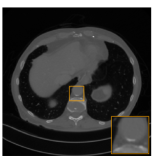

Fig. 3.1: Reconstruction from simulated data.

The first case we consider is the case of noise-free data. Figure 3.1 shows the FBP reconstruction uFBP=𝐊(y)subscript𝑢FBPsuperscript𝐊𝑦u_{\mathrm{FBP}}=\mathbf{K}^{\sharp}(y) and the reconstruction with the full network upost=𝐍(uFBP)subscript𝑢post𝐍subscript𝑢FBPu_{\mathrm{post}}=\mathbf{N}(u_{\mathrm{FBP}}) where 𝐍𝐍\mathbf{N} is defined as above and the aNETT reconstruction uaNETTsubscript𝑢aNETTu_{\mathrm{aNETT}}. Comparing the results we see that the output of the problem adapted network upostsubscript𝑢postu_{\mathrm{post}} and the aNETT output uaNETTsubscript𝑢aNETTu_{\mathrm{aNETT}} are visually identical. This is because, the test image u𝑢u is close to the training data and therefore the considered training procedure implies that upostsubscript𝑢postu_{\mathrm{post}} is close to minimizer of the sparse aNETT. In comparison to the FBP we see that the aNETT was able to completely remove all the artefacts and yields an almost perfect reconstruction.